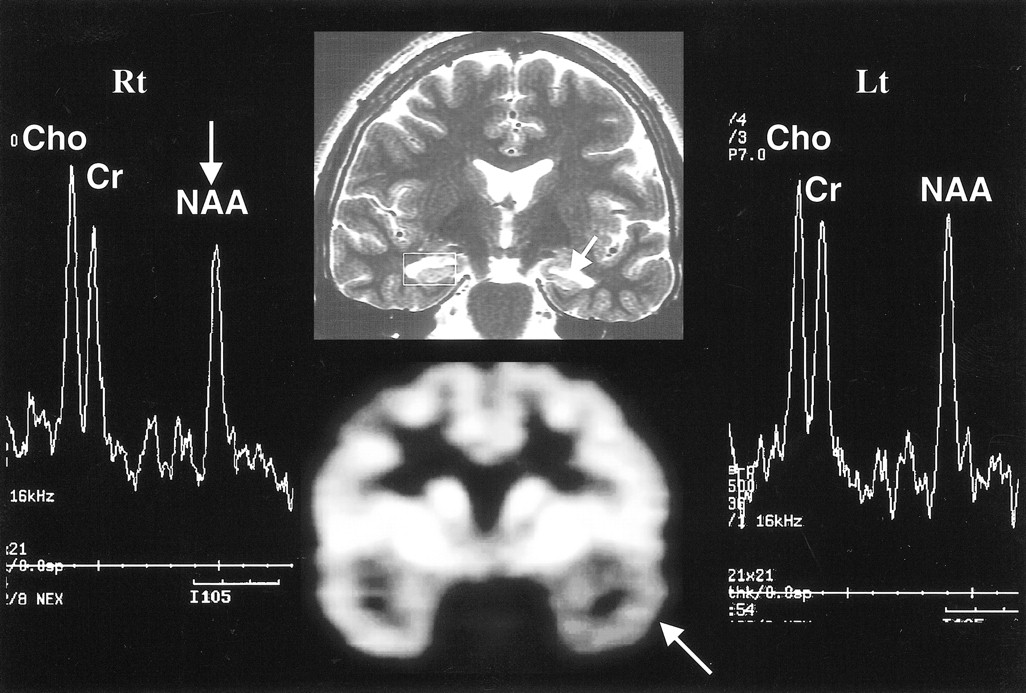

Concordance among MR imaging, MRS, and PET in right hippocampal sclerosis. Oblique coronal T2-weighted MR image (top row, middle) shows right hippocampal sclerosis (arrow), in concordance with PET scan (bottom row, middle), which shows decreased metabolism in right temporal lobe (arrow). The MR spectrum from the right hippocampus (Rt) shows marked decrease in NAA/Cho ratio (arrow). The MR spectrum from left hippocampus is normal (Lt)